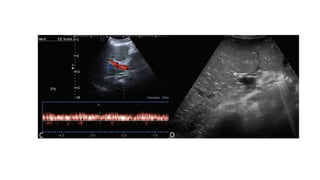

• US and Doppler-

• It helps identify patency and direction of flow in relevant vessels and

frequently identifies collaterals.

• The normal portal vein flow on Doppler is always hepatopetal with a

fairly uniform flow and slight undulation/phasicity due to respiration

and cardiac activity.

• The normal mean flow velocity is 12 to 18 cm/s (or peak velocity from

20 to 40 cm/s).

• As PHT starts to develops, the flow in the portal vein decreases and

loses normal undulation and becomes monophasic.

• With more severe PHT, there will be reverse/hepatofugal flow.

• The portal vein diameter should be measured at the point it crosses

anterior to the IVC.

• For Doppler evaluation, the most important technical requirement is

the need to keep the angle of insonation less than 60 degrees.

• Scanning should be done in gentle respiration.

• Performing scan in arrested or deep inspiration can increase the

portal vein caliber and halt or even reverse the flow, and hence should

be avoided.

• #17 SPLENOPORTAL AXIS-COLOR DOPPLER STUDY